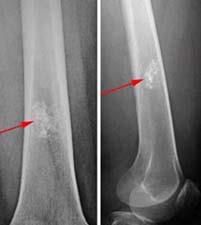

Treatment will depend on your symptoms, age, and general health. It will also depend on how severe the condition is. Treatment may include: Surgery. In some cases, surgery is done when bone weakening is present or fractures occur. Bone grafting. This is a surgery where healthy bone is taken from another part of the body and transplanted into the affected area. If there is no sign of bone weakening or growth of the tumor, your healthcare provider may simply keep a close watch on your condition. However, follow-up with repeat X-rays may be needed. Some types of enchondromas can develop into cancerous bone tumors later. Careful follow-up with your healthcare provider is often recommended.